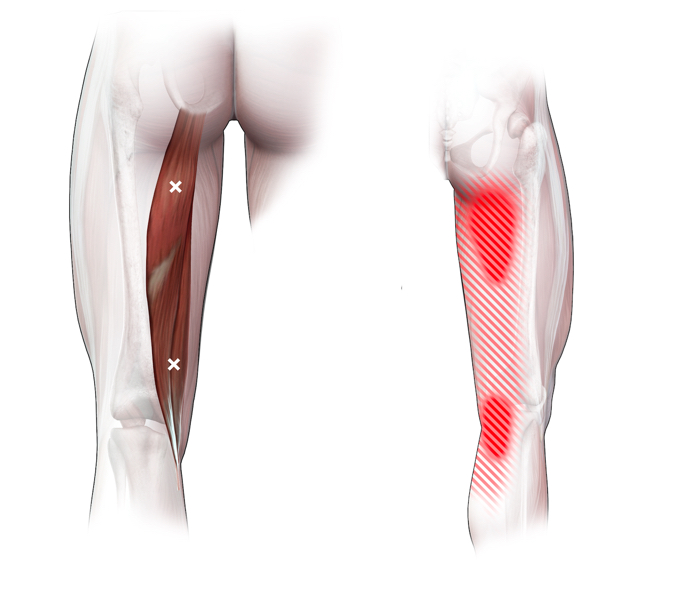

Spieren (Nederlands)

Spieren (nederlands)

Spieren (Latijn)

Spieren (latijn)